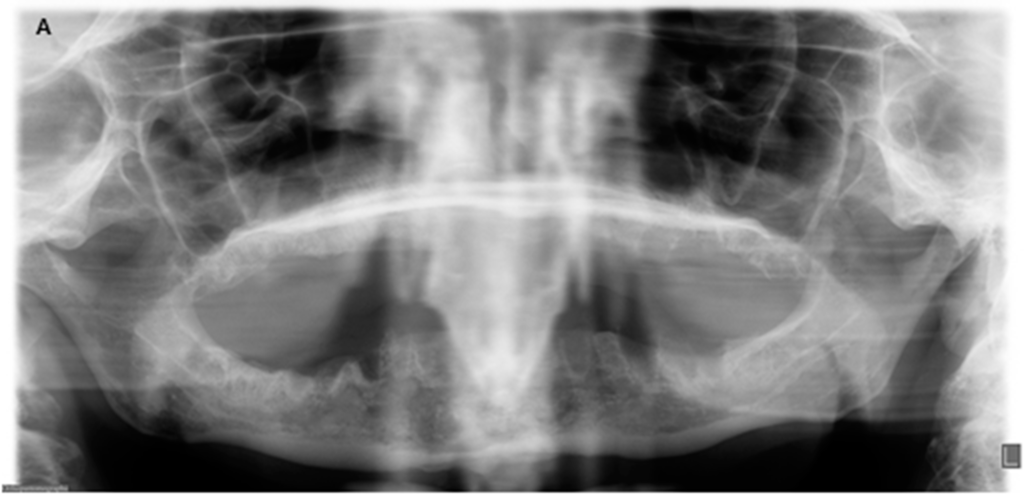

Figure 2.

Radiologic findings before surgery and nine months after surgery. (A) Panoramic radiograph with extensive osteolysis, extending from region 46 to 34 up to the inferior border in the region of the symphyse; (B) Panoramic radiograph nine months post-operatively with healed, smooth edges of the mandibular body.